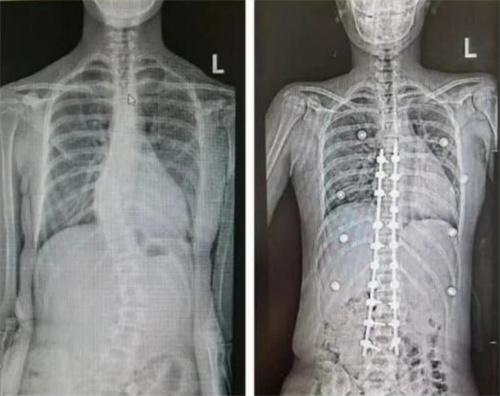

在講到馬凡綜合癥時,陳主任表示這種癥狀會導致孩子的骨骼發育出現異常情況,這種癥狀和脊柱側彎以及先天性脊柱畸形有著極大的不同之處。在去做矯正手術時,這種癥狀無疑增加了手術的難度,在和可可的父母進行商議之后,最終陳主任給可可進行了手術,幸運的是在手術之后,可可的情況恢復的較為不錯。